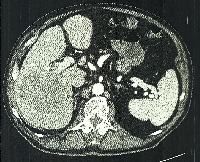

Πρόκειται για άνδρα ασθενή 73 ετών ο οποίος, στα πλαίσια διερεύνησης αισθήματος εύκολης κόπωσης, διαπιστώθηκε (MDCT, MRI) ότι έφερε ευμεγέθη, μονήρη, συμπαγή μάζα στο δεξιό λοβό του ήπατος, με μέγιστη διάμετρο 13 cm και απεικονιστικά χαρακτηριστικά αδενώματος (εικόνες 1 & 2) . Είχε ιστορικό συνεχούς κατανάλωσης αλκοοόλ με ήπια διαταραγμένη ηπατική βιοχημεία. Υποβλήθηκε σε δεξιά ηπατεκτομή (σωστική παρεγχύματος, parenchymal sparing) με τη χρήση της τεχνικής επικρεμμάμενου ήπατος (hanging maneuver, εικόνα 3). H παθολογοανατομική εκτίμηση του παρασκευάσματος (εικόνες 4 & 5) επιβεβαίωσαν την αρχική διάγνωση. Ο μετεγχειρητικός σχετικός όγκος του ηπατικού υπολείμματος (εικόνα 6) ανήλθε στο 72% του αρχικού όγκου του οργάνου. Ο ασθενής έλαβε εξιτήριο την 6η μετεγχειρητική ημέρα.